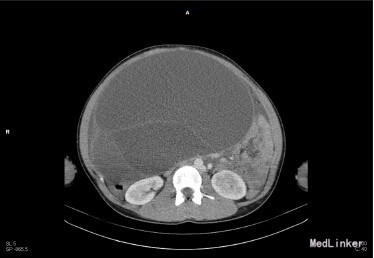

体格检查:腹部膨胧,触及骨盆延至剑突的质硬包块。 腹部 B 超提示骨盆至剑突巨大多房性囊性包块。CT 可见包块几乎占据整个盆腹腔。但 B 超和 CT 均不能判断这个巨大包块起源于何处。 实验室检查:CA-199:237 U/ml (0-33U/ml),CA-125:144U/ml(0-16.3U/ml),CEA、AFP、HCG 均在正常范围内。血常规、肝肾功能指标未见明显异常。

行正中切口剖腹探查术,术中见包块表面光滑,来源于左侧卵巢,右侧卵巢外观正常,探查骨盆,腹壁,横膈、腹膜未见种植转移灶,腹腔无游离积液。 因包块巨大,同侧几乎无正常卵巢组织,遂行左侧输卵管卵巢切除术,术后见包块大小 40*25*25cm,重量 9kg,大体可见包块表面光滑,灰白色,表面血管增生丰富。巨检:肿瘤呈多房性,囊内含粘稠液体。组织学检查见囊壁组织内衬粘液上皮,未见乳头样生长。 术后诊断为:卵巢粘液性囊腺瘤。